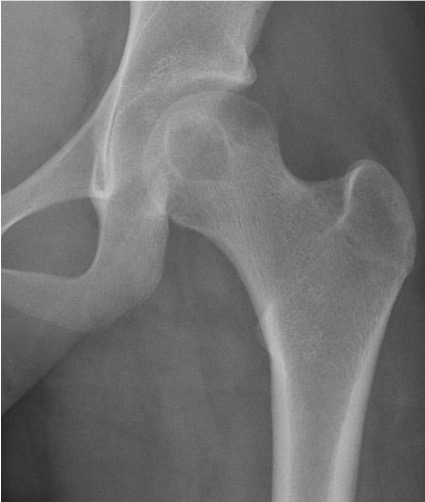

Pre-biopsy Radiology Finding:

Round lytic lesion in the femoral head